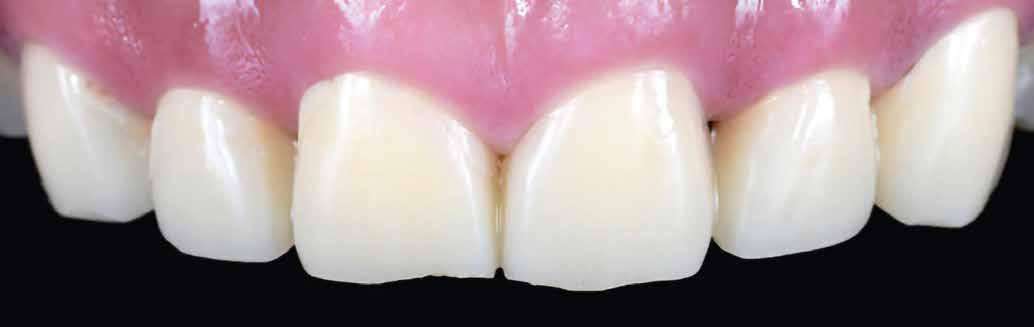

KIRÁLYKATEGÓRIA –FRONTFOG-MEGOLDÁS

Implantátum-protetikai ellátás digitális tervezéssel

Egyetlen frontfog pótlása most is – akárcsak korábban – a királykategóriába tartozik. Bármely kis formai vagy színhiba kíméletlenül megmutatkozik minden mosolynál. Ezzel hihetetlen szintet nő, vagy csökken a páciens életminősége. Stefanie Flentje esetbemutatása ismerteti, hogyan valósíthatunk meg sikerrel implantátum elhorgonyzású borítókoronát a frontterületen.

A 64 éves hölgypáciens esztétikus pótlást kívánt 21-es foga helyén, amelyet balesetet követően 2022-ben távolítottak el. Az összes foga egészséges és vitális volt, így a 21-es régióba implantátum került, amelyre cirkónium-dioxid koronát terveztünk. Az implantátum típusát, pozícióját, átmérőjét egyedi anatómiai adottságainak és az adott helyviszonyoknak megfelelően választottuk meg.

Előkezelés

2023 elején került behelyezésre a 21-es régióba egy Camlog Tissue Level implantátum, 4,3 mm átmérővel és 13 mm hosszal. Az eseménymentes gyógyulást követően az implantátum csontosodását a Periotest-eljárással ellenőriztük, majd hagyományos zárt kanalas lenyomatvétel után ideiglenes ellátás készült (2–4. képek).

építményhez gyári Camlog titánbázist használtunk, amit előzetesen befedtünk DCMhotbond fusio connect spray-vel. A titánbázis felületi kondicionálásához alkalmazott anyag kiváló, résmentes és tartós kötési alapot teremt a bázis és a rá készülő cirkon konstrukció között1. A cirkónium-dioxid egyedi felépítmény tervezését primer teleszkóp koronaként választottuk ki a CAD-szoftveres lehetőségek tárából. A felső mintát a beszórt titánbázissal ínymaszkkal és anélkül is beszkenneltük, akárcsak az antagonista mintát. A titánbázist hárompontos vonatkoztatással illesztettük a digitális mintába, majd megállapítottuk a behelyezési irányt és az illesztő paramétereket (7–13. képek).

Tervezés és kivitelezés a laboratóriumban

Az implantátumról készült lenyomat, valamint az alginát antagonista fertőtlenítése után szuperkemény gipszből az előírások szerint elkészültek a minták. A felső mintát a technikai implantátum körül levehető ínymaszkkal készítettük. SAM-arcív segítségével habituális okklúzióba helyeztük a mintákat. A felső mintát előkészítettük a digitális tervezéshez, enyhén megformáltuk az emergenciaprofilt, hogy tökéletes legyen a rózsa-fehér esztétika. A fogszínt – a pácienssel történt egyeztetést követően – dokumentáltuk.

Digitális tervezés

A mintát beolvastuk (D1000, 3Shape), majd megterveztük a munkát (3Shape Dental System) (6. kép). A fel -

Próba és behelyezés

A felépítmény próbája és behelyezése a szájba a segédelemmel történik. Az emergenciaprofil kezdetben még

enyhén anémiás (vérszegény – a ford.), de gyorsan újra telítődik, tökéletesen illeszkedve a szituációhoz (36–42. képek)

A páciens a DD cube One koronát választotta, ami szín és transzparencia szempontjából is nagyon harmonikusan illeszkedett a teljes képhez (43–44. képek)